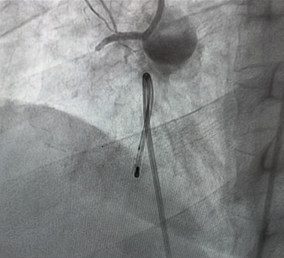

Given the complete AVB, a temporary transvenous pacing wire was promptly placed to ensure adequate cardiac output.

The patient was transferred to the catheterization laboratory for emergent coronary angiography. This revealed a complete thrombotic occlusion of the first segment of the right coronary artery (RCA) (Figure 3). A percutaneous coronary intervention (PCI) was performed, with successful placement of a drug-eluting stent (DES), achieving TIMI grade 3 flow. (Figure 4).

Figure 3: Coronary angiogram showing an occlusion of CDI